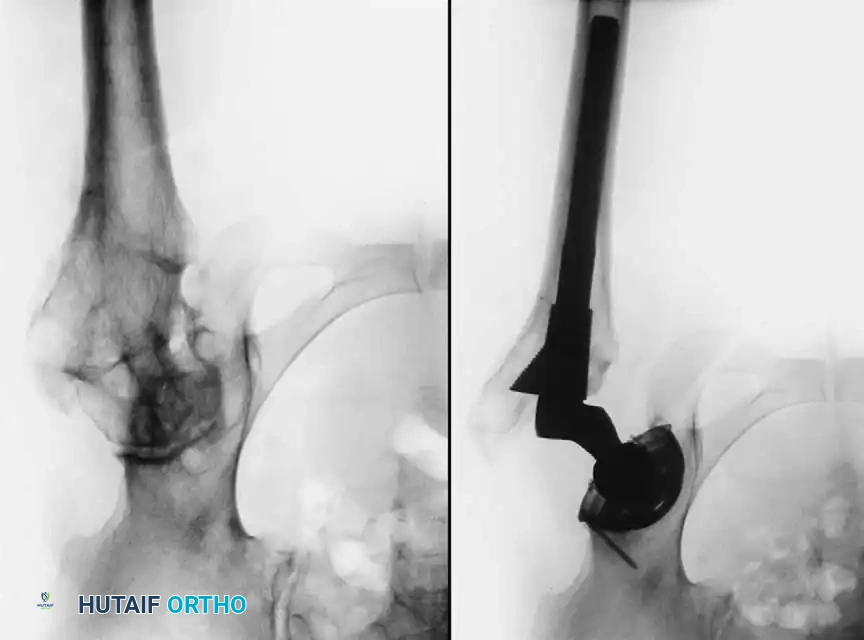

Fig. 7-74 Primary protrusio acetabuli. Otto pelvis in 52-year-old woman. Femoral head has migrated medial to ilioischial (Kohler) line. Hip motion is severely limited.

Principles of Reconstruction

The surgical management of protrusio acetabuli is technically demanding and relies on three non-negotiable biomechanical principles:

1. Restoration of the Anatomic Hip Center: The hip center of rotation must be lateralized and brought inferiorly to its true anatomic position to restore abductor mechanics and minimize joint reactive forces.

2. Peripheral Rim Fixation: The implant must be supported by the intact, structurally sound peripheral rim of the acetabulum, bypassing the deficient medial wall.

3. Medial Wall Reconstruction: Cavitary and segmental defects of the medial wall must be reconstituted, typically utilizing impaction bone grafting (autograft from the resected femoral head or allograft).

Fig. 7-75 Reconstruction for protrusio acetabuli deformity. A, Diagrammatic representation of medial wall grafting and lateralized cup placement.

Fig. 7-75 Reconstruction for protrusio acetabuli deformity. B, After total hip arthroplasty. Hip center was restored to more lateral and inferior position. Large acetabular component allowed rim fixation without need for screws, and medial deficits were grafted with cancellous autograft from femoral head with excellent incorporation.